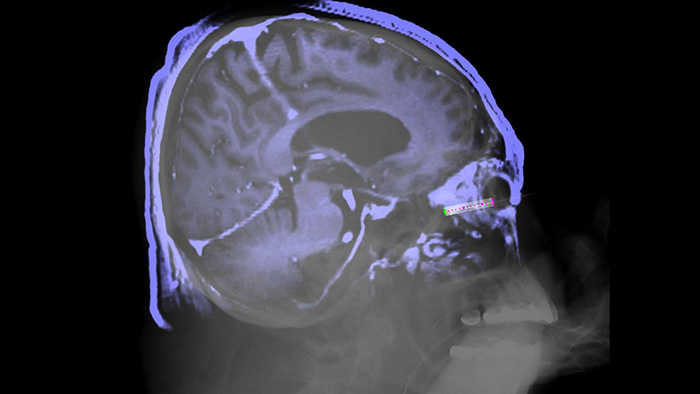

During neurosurgery, the goal is to see clearly, while managing safety for all involved. The industry leading Azurion 7 biplane X-ray system is designed to enhance treatment and support effective guidance as you work. The perfect fit design of the FD20/15 detector allows the 15” detector to be positioned close to the patient’s head, covering the head from cranium to cervical. Seamlessly control all relevant applications from a single touch screen at table side, to help make fast, informed decisions in the sterile field.

XperGuide offers live 3D image needle guidance, letting you bring percutaneous needle procedures into the Hybrid OR. It overlays live fluoroscopy and 3D soft tissue imaging data from previously acquired CT or MR scans or Philips XperCT, providing information on the needle path and target.